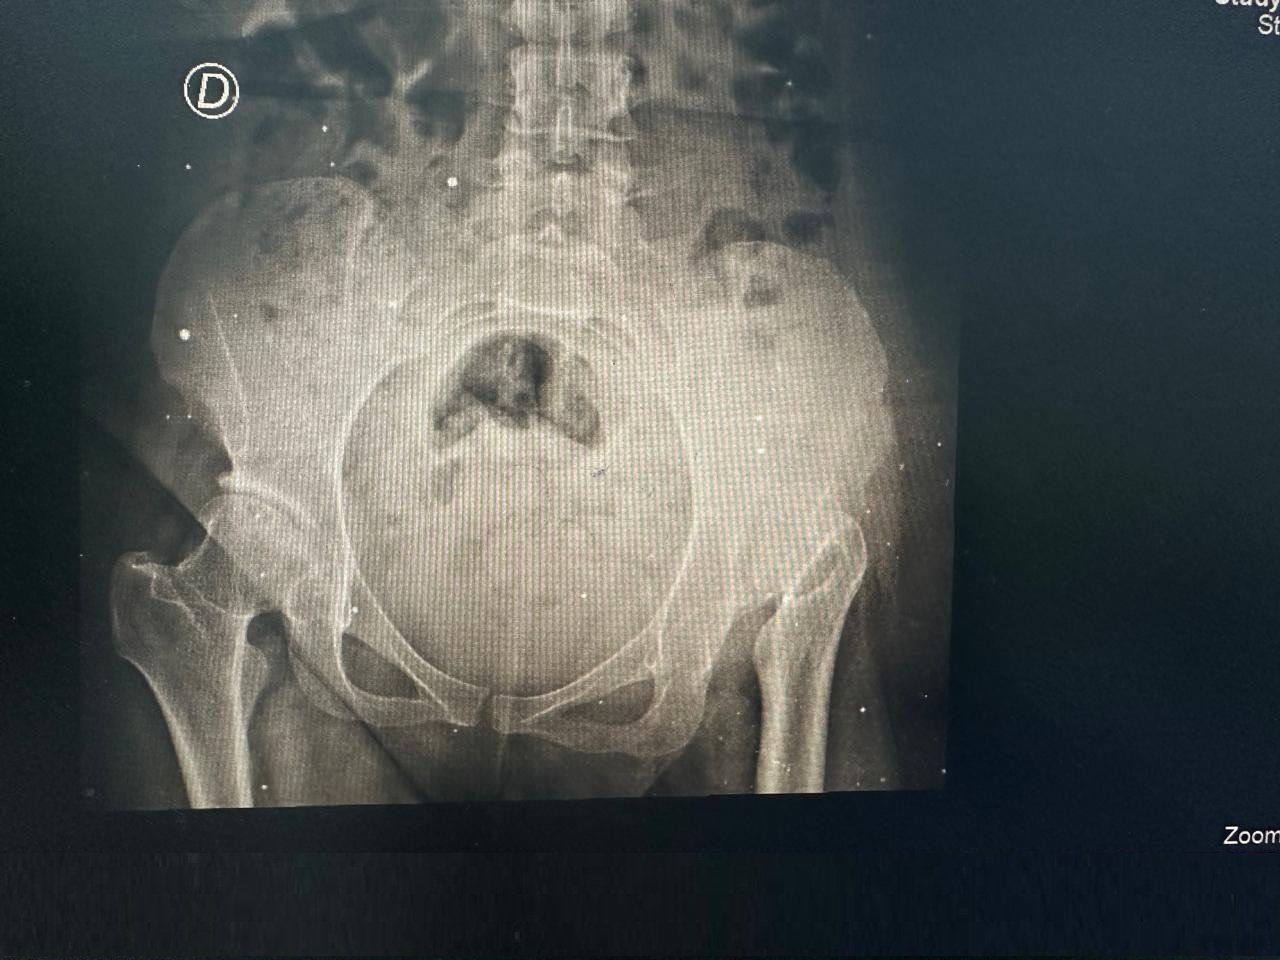

Antes Radiografía preoperatoria mostrando desgaste articular severo en cadera derecha - Dra. Ana Luz Bernabe

Reemplazo Articular

Artroplastia Total

de Cadera Derecha

• Perfil del Paciente: Femenino, 29 años. Cuadro de dolor severo de larga evolución.

• Diagnóstico: Limitación funcional severa para la marcha y actividades de la vida diaria.

• Procedimiento: Reemplazo total de cadera izquierda.

• Evolución (3 años): Reintegración total a sus actividades con excelente estabilidad y ausencia de dolor.